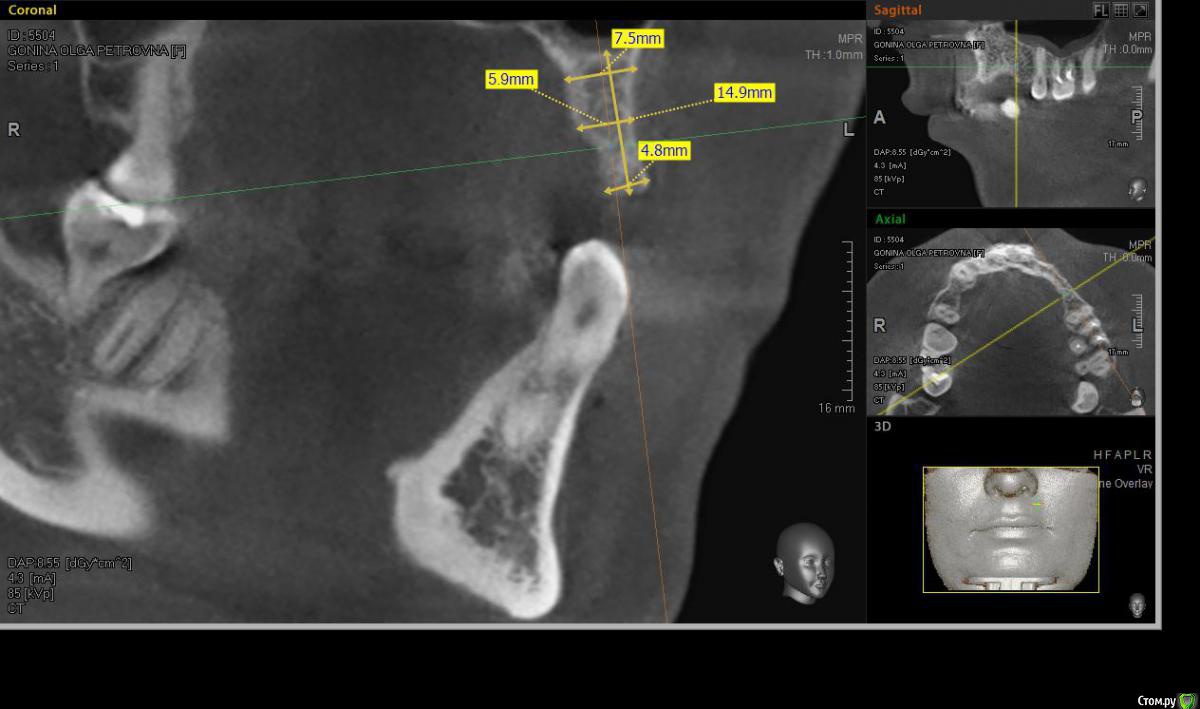

denis1987 Опубликовано 6 декабря, 2014 Поделиться Опубликовано 6 декабря, 2014 Здравствуйте, коллеги. У пациентки частичная вторичная адентия на верхней челюсти слева, отсутствующие зубы 22,23,24. С ортопедом запланировали имплантацию. Снимки прилагаю. Форма альвеолярного гребня вроде как то не особо располагает для расщепления, но все таки хочу попробовать. За ответы заранее спасибо. Ссылка на комментарий